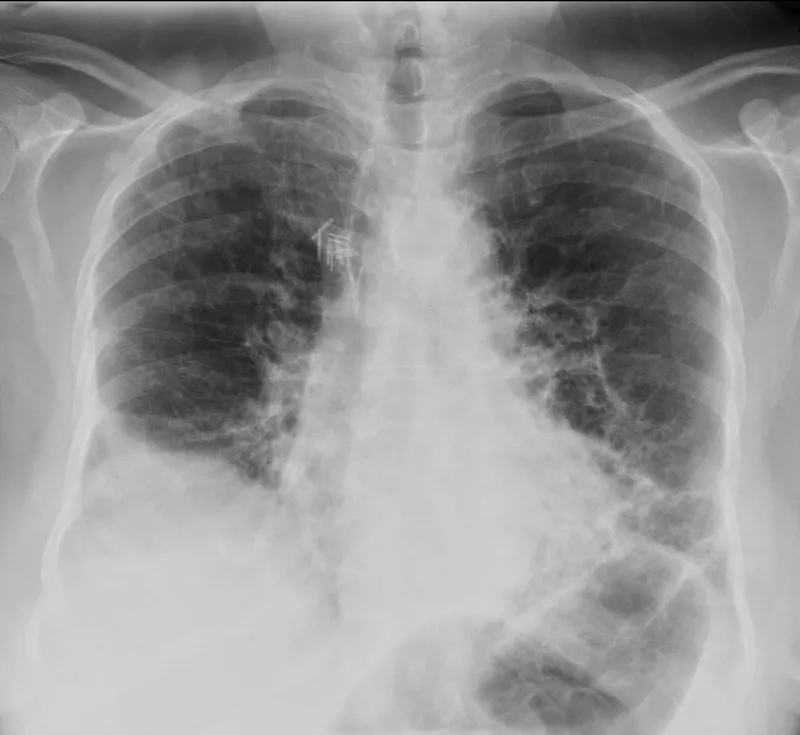

Image of the disease occupational lung diseases